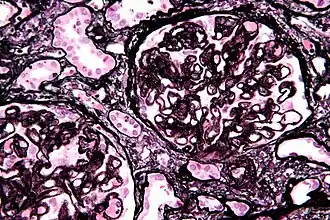

Histologia da membrana basal glomerular com depósitos de complexos imunes (Tinção de Jones)

Ao microscópio a membrana basal dos glomerulos está cheia de depósitos de complexos imunes, com furos cada vez maiores e "espinhosa"

Histologia

A principal característica microscópica é o espessamento global da membrana basal glomerular com deposição de imunocomplexos nas alças capilares. Atualmente acredita-se que os pacientes portadores de GNM produzam anticorpos contra antígenos presentes nos podócitos ou contra proteínas estranhas ligadas a membrana basal glomerular, levando ao desenvolvimento dessa glomerulopatia.